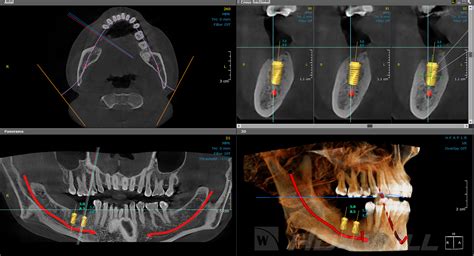

Una Tomografía Axial Computarizada (TAC) es un examen que utiliza rayos X para obtener imágenes en 2D y 3D de las estructuras internas de la boca. Es una herramienta valiosa para evaluar la salud dental y planificar tratamientos.

¿Por qué es Necesario un TAC Dental antes de un Implante?

Antes de proceder a la colocación de uno o varios implantes dentales, necesitaremos saber si tu mandíbula cuenta con la cantidad y densidad suficiente de hueso como para darle soporte.